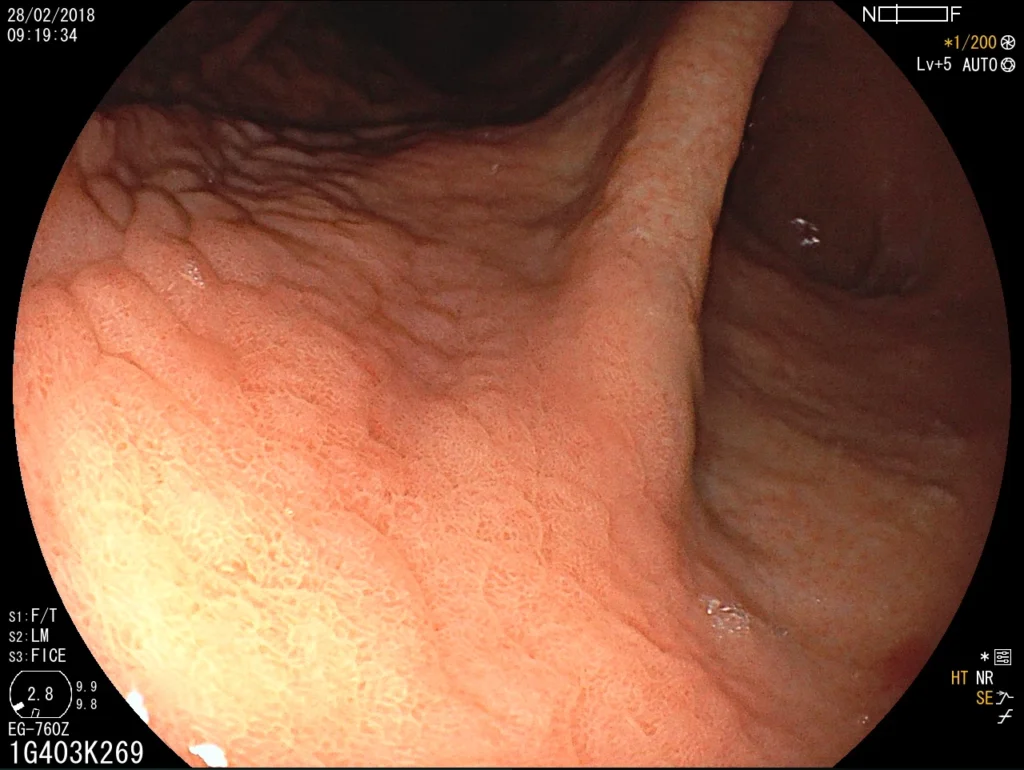

Introducción del gastroscopio bajo visión directa para examinar esófago, estómago y duodeno.

Toma de biopsias de mucosa gástrica o de lesiones encontradas.